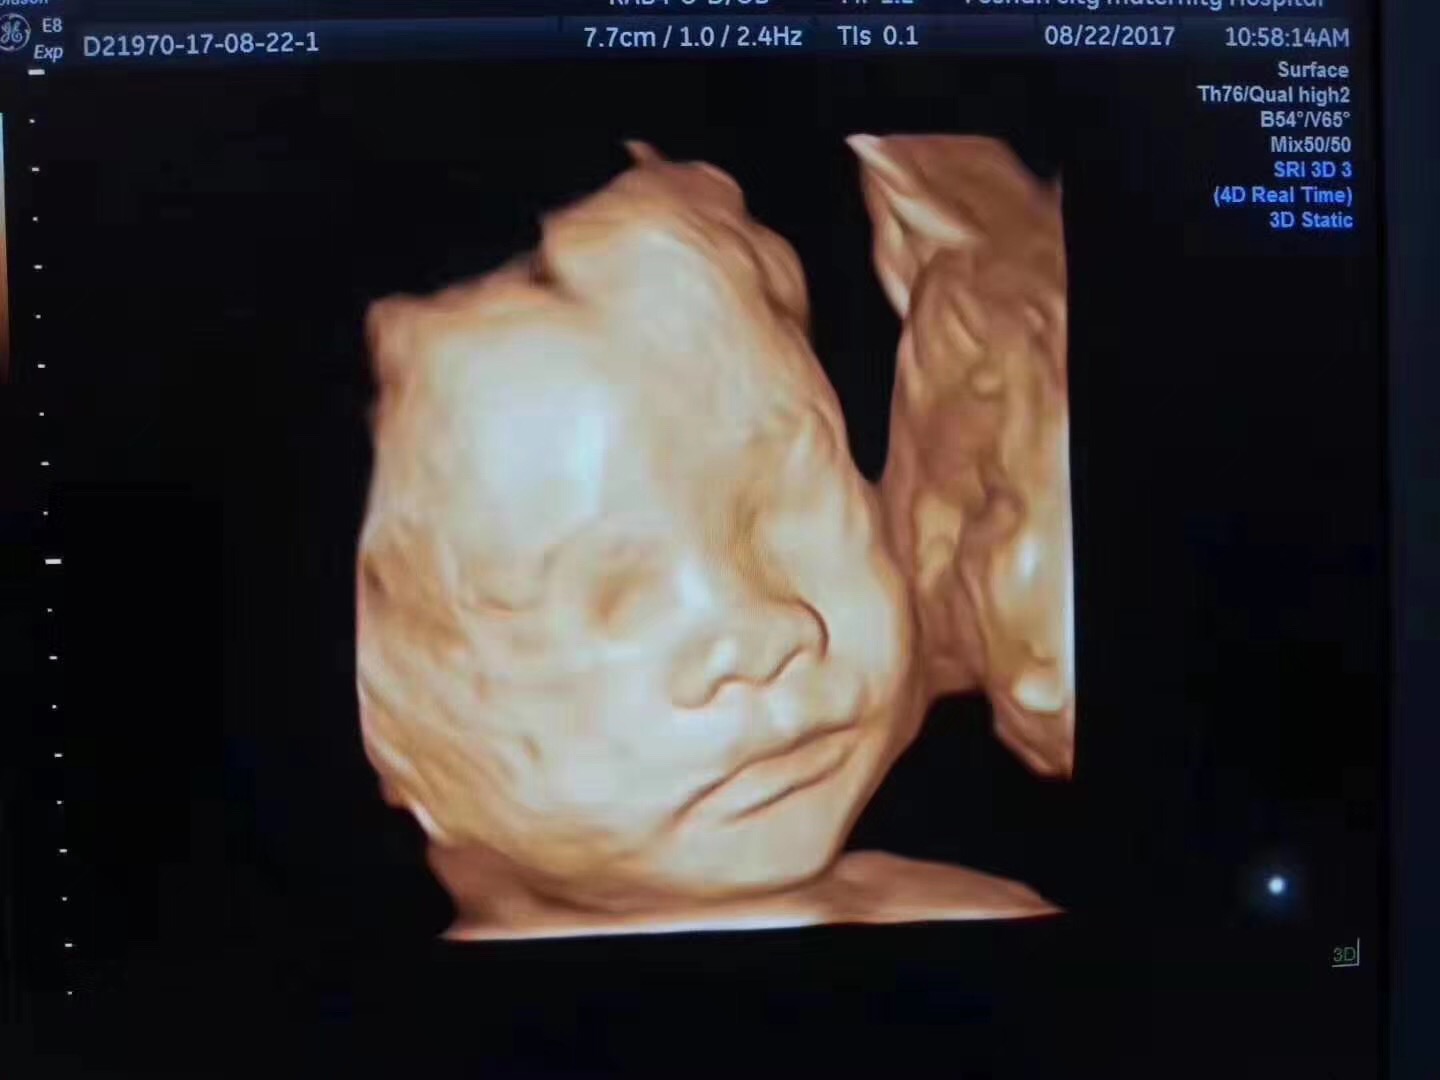

产检NT、唐筛、四维彩超、糖耐量试验,你都做了吗

产检NT、唐筛、四维彩超、糖耐量试验,你都做了吗?